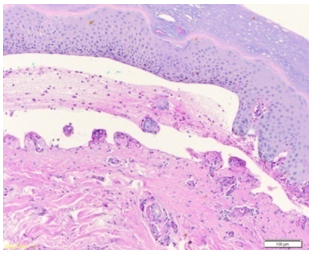

The blisters were not painful, but he did have some itching. He denied fever, chills, sore throat, cough, diarrhea or night sweats. He also denied recent ingestion of new medications, sick contacts, similar rashes in family members, dietary change, exposure to chemicals, or tick or mosquito bites. On presentation, he was afebrile and hemodynamically stable. Vitals were: Blood Pressure 106/76 mm of Hg, Heart rate 90 beats per minute, Respiratory rate 20 per minute, and Temperature was 97.2F. Notable labs included WBC 6.5k, Hgb 10.1, Hct 31.3, Plt 165k, Na 139, K 4.3, BUN 13.1, and Cr 1.56 (baseline 1.4-1.5), CRP 18.88, and ESR 29. HIV, RPR and Hepatitis serology were nonreactive. Procalcitonin was 0.07. Autoimmune screen including ANA screen, Rheumatoid factor, and Anti-CCP IgG antibody was all negative. Immunoglobulin levels except IgG subclass 4 were all within normal limits. IgG subclass 4 was elevated at 338. Herpes simplex virus type 1 and 2 DNA was not detectable. Dermatology team performed a biopsy of the bulla. Pathology reported as leukocytoclastic vasculitis and features suggestive of bullous pemphigoid or bullous drug eruption (Figure 4-6) and the patient was started on dexamethasone.

Figure 6: Punch biopsy with subepidermal clefting that contains a few eosinophils, lymphocytes and occasional neutrophils. The dermis shows a mild perivascular infiltrate with eosinophils and lymphocytes. (Hematoxylin & Eosin stain, magnification 100X). Features suggestive of bullous pemphigoid or bullous drug eruption. Immunofluorescence studies were suboptimal but showed linear pattern along the basement membrane with the C3 antibody.